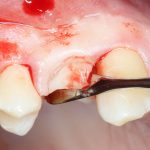

С учётом клинических условий, мы подобрали к установленному имплантату формирователь Slim (без расширений) высотой 3 мм:

Для окончательного формирования десневого контура, осталось только наложить швы.